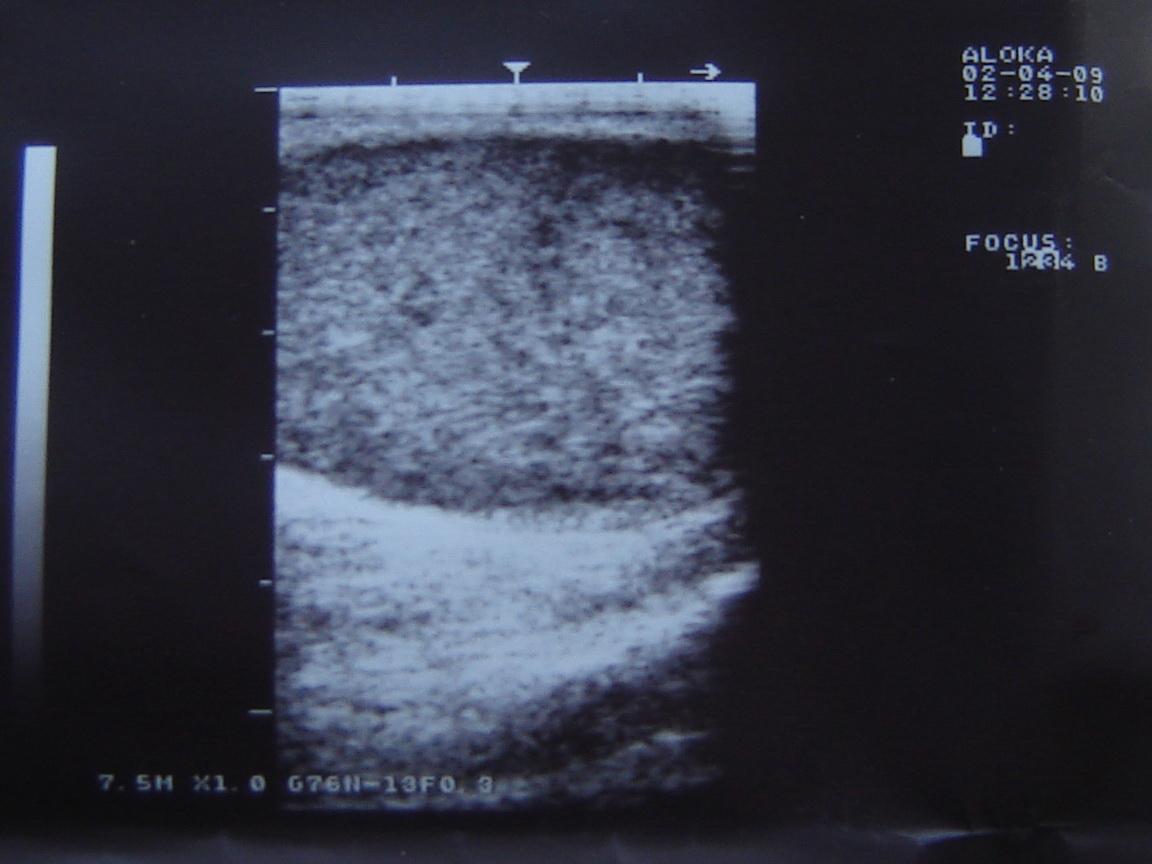

Уважаемый Алексей! По одному УЗИ не ставится диагноз. Надо сдать кровь на альфа-фетопротетеин и хореонический гонадотропин, сделать доппрерографию яичка. Проявите онконастороженность. Все лечится, если вовремя выявить. Напишите нам о результатах обследования.